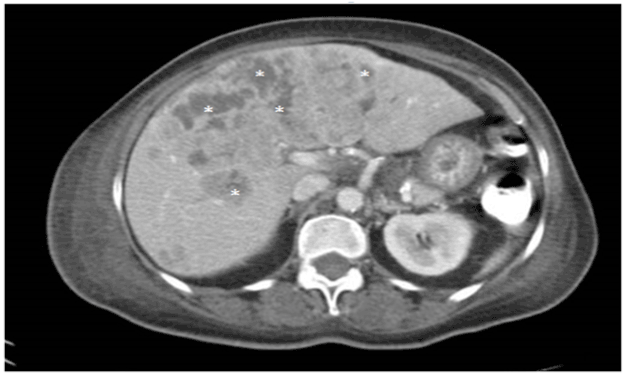

A 72 year-old-female presented with intermittent chest pain at rest and generalized fatigue for 3 days. Patient had a medical history significant for diabetes mellitus, chronic kidney disease and was recently diagnosed with poorly differentiated NET of an unknown primary site. On presentation, she had a heart rate of 105 beats per minute, a blood pressure of 137/87 mmHg, a respiratory rate of 18 breaths/min, a temperature of 98.2 F and oxygen saturation level of 94 % on room air. Lung examination showed normal breathing sounds. Cardiac examination showed rapid and regular heart beats, with normal heart sounds and no audible murmur. She had no jugular venous distention or peripheral edema. The rest of the exam was unremarkable. Chest X-ray was normal. Electrocardiogram showed normal axis, sinus tachycardia with associated 1-mm ST-segment depression in infero-lateral leads (Figure 1). Transthoracic echocardiogram revealed normal left ventricular ejection fraction (60%), with segmental wall motion abnormality involving basal and mid inferior wall, normal valvular morphology and function as well as normal right ventricle size and function. Computerized tomography angiogram of the chest didn’t show any evidence of pulmonary embolism.

Pertinent laboratory studies revealed hemoglobin of 12 g/dl, white blood cell count of 14 x 103 cells/ull, procalcitonin < 0.05 (normal < 0.1), serum creatinine of 1.2 mg/dl, elevated troponin level which peaked at 8.04 ng/ml, serum serotonin of 1280 ng/ml, chromogranin A of 114500 ng/ml and 24 hours urinary 5-HIAA of 332 mg. Owing to poor prognosis and poor general condition, decision was made to conservatively mange her NSTEMI. She was started on a somatostatin analogue and a beta-blocker, with secondary improvement in her symptoms.